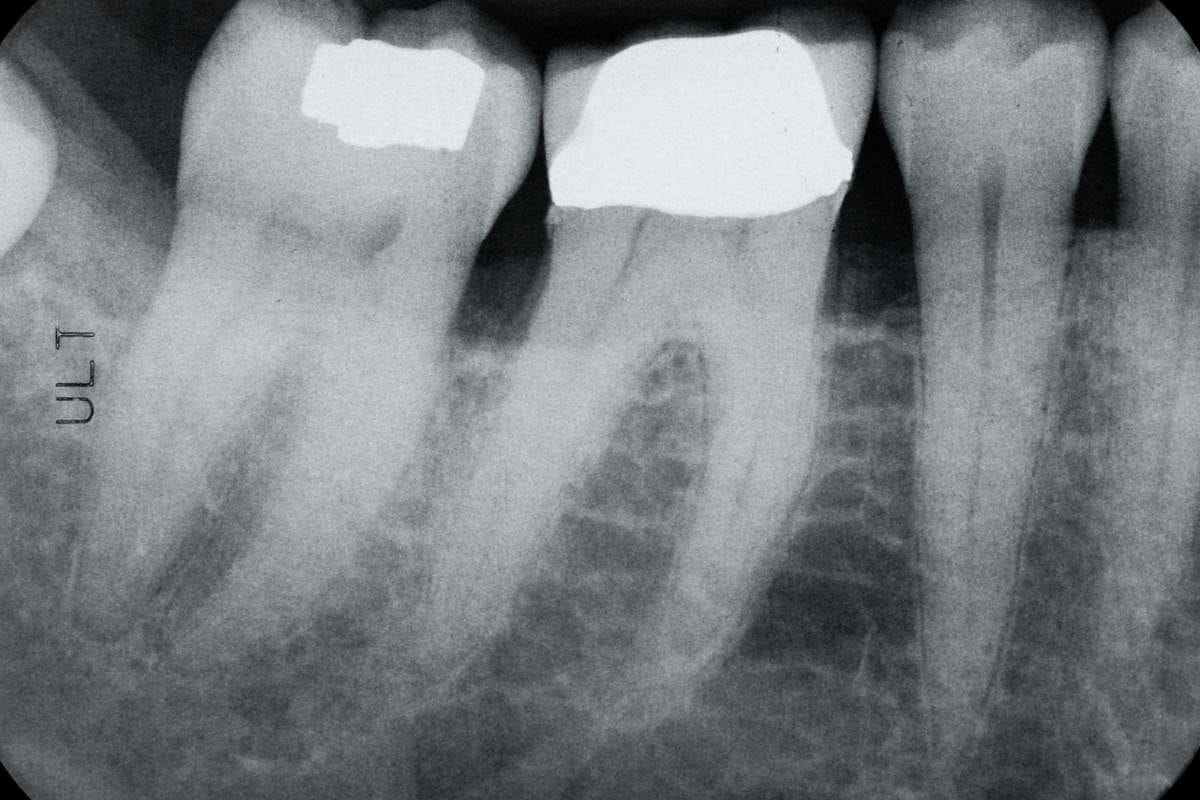

Специалисты по пародонтологии ставят диагноз, измеряя глубину десневых карманов и оценивая потерю костной ткани челюсти с помощью рентгеновских снимков. Во время диагностики также проводится анализ налёта и зубного камня.

Воспаление, отступление, чувствительность и инфекции десен оцениваются специалистами по пародонтологии. Пародонтология также контролирует состояние десен перед имплантацией. Этот процесс лечения охватывает не только десны, но и челюстную кость.

Атрофия костной ткани челюсти